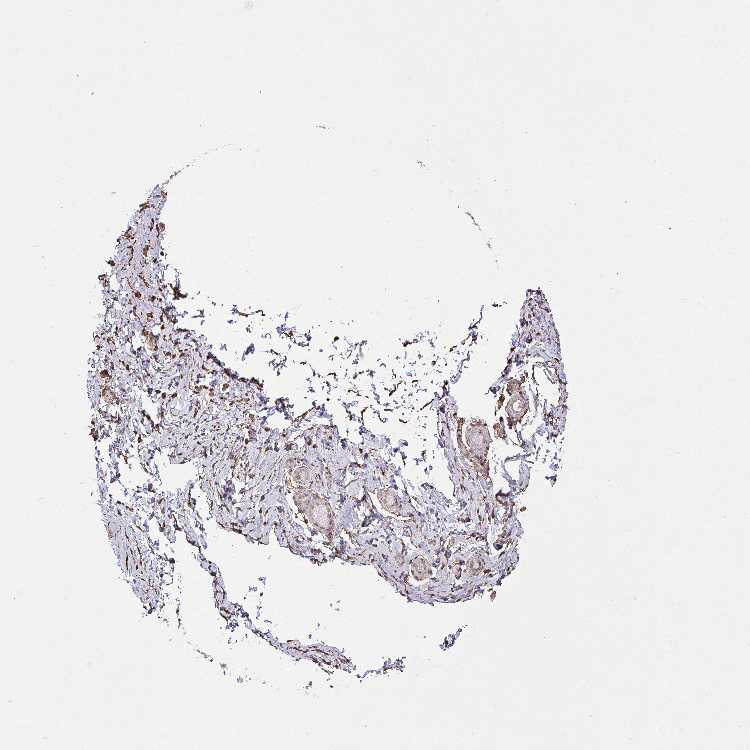

SOFT TISSUE 1 - Antibody stainingi

Antibody staining in the annotated cell types in the current human tissue is reported as not detected, low, medium, or high, based on conventional immunohistochemistry profiling in selected tissues. This score is based on the combination of the staining intensity and fraction of stained cells.

Each image is clickable and will lead to virtual microscopy that enables deeper exploration of all samples and also displays staining intensity scores, fraction scores and subcellular localization as well as patient and tissue information for each sample.

Antibody HPA035330Antibody CAB003677

Fibroblasts MediumNot detected